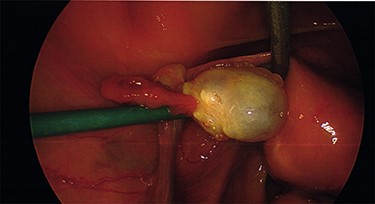

Intraoperative findings were inconsistent with all pre-operative ultrasound diagnoses. Both ovaries appeared suspicious for malignancy with cystic lesions covering the surface of the right, while the left appeared to contain two smaller cysts (Figs 3–5). There were no hydrosaplinges or free fluid within the pelvis. Given the abnormal features of the ovaries, the surgeon proceeded with the laparoscopic BSO without spillage. Pelvic washings were performed, though there were no atypical peritoneal or omental lesions for biopsy.

The intra-operative photos demonstrating the cystic appearance of the left ovary.